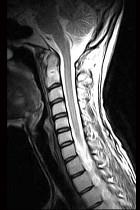

问题 女,29岁,有午后发热,夜间盗汗,消廋等,枕颈部疼痛,活动头部时时加重,休息后减轻,请结合所提供的图像,选择最佳选项 ( )

选项 A、寰枢椎结核 B、骨髓瘤 C、寰枢椎骨转移 D、寰枢椎退行性变 E、未见异常

答案 A